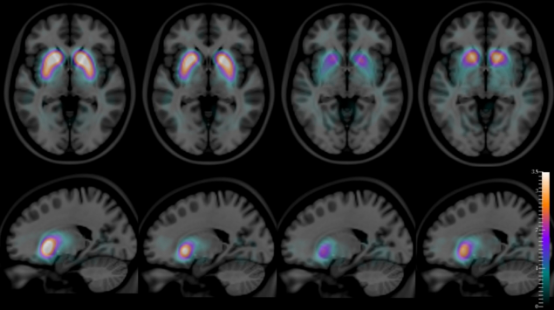

據報道,GE Healthcare 的 DaTscan 是美國食品和藥物管理局 (FDA) 批準用于疑似路易體癡呆患者的第一種放射性藥物示蹤劑。

一種與單光子發射計算機斷層掃描 (SPECT) 結合使用的新興顯像劑可能有助于提高對路易體癡呆癥的檢測,這種疾病影響了大約 20% 的癡呆癥患者,據報道,這些患者中有 70% 由于癥狀和體征重疊而被誤診與其他神經退行性疾病。

DaTscan (GE Healthcare)最近獲得了美國食品和藥物管理局 (FDA) 的擴大批準,用于疑似路易體癡呆患者。 GE Healthcare 表示,DaTscan 是第一個被 FDA 批準用于這種情況的放射性藥物示蹤劑。

據 GE Healthcare 稱,DaTscan 先前已獲得 FDA 批準,用于在患有疑似帕金森綜合癥的成人的 SPECT 成像中顯示多巴胺轉運蛋白。